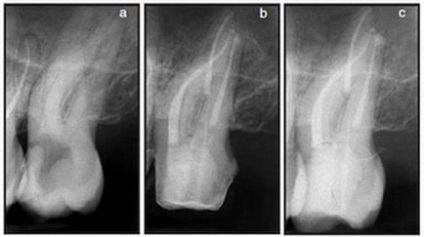

Klinikai eset №1.

a) A második felső állkapocs kisőrlő jobb jeleivel akut gyulladás a cellulóz.

b) meghatározása munkahossz egy acél fájlt. Megjegyezzük, hogy a gyökere a fog erősen ívelt, és van egy kis vastagságú dentin falak csúcsi kétharmadát.

c) Mtwo 20.06 eszköz be a munkahossz.

d) kitöltése a gyökércsatorna rendszer. Az eszköz Mtwo 40.04 használtunk master file. Mentése csatorna anatómia és szövet-megtakarító gyökér arányt értek el, még viszonylag nagy csúcsi kiterjesztése.